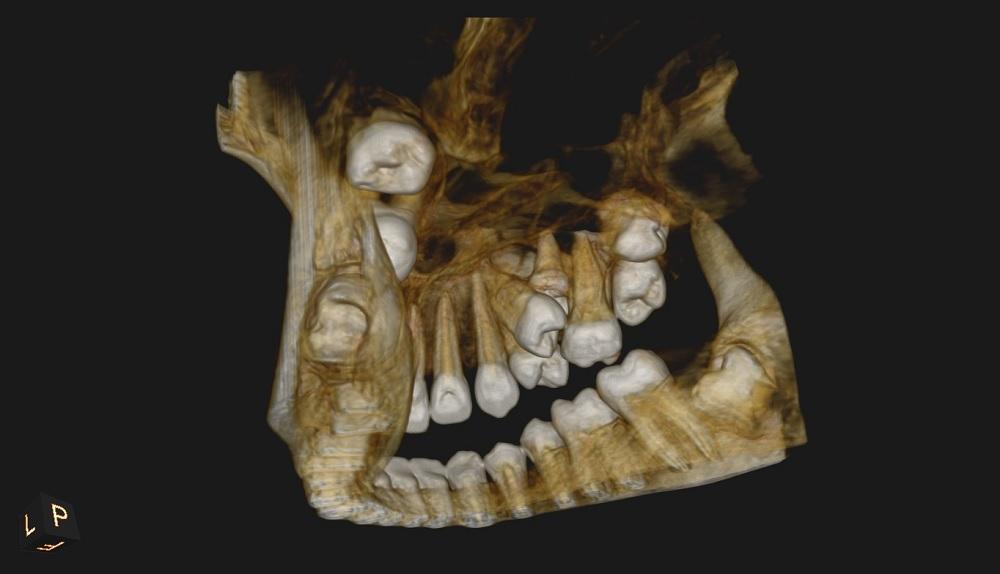

CBCT szczęki.

Badanie tomografii stożkowej (CBCT) uwidoczniło reinkluzję zęba 55 powodującą zaburzenia wyrzynania zębów stałych.

Na ząb reinkludowany wskazano ząb trzonowy mleczny 55 ze względu na położenie, budowę zęba oraz obraz korzenia policzkowego

przedniego, wskazujący na częściową resorpcję.

Ząb reinkludowany bywa również określany mianem zęba zatopionego lub zagłębionego ponieważ isotą zaburzenia jest odsuwanie się od

płaszczyzny zgryzu wcześniej wyrzniętego zęba.

W opisywanym przypadku mamy do czynienia z reinkluzją całkowitą, w której ząb w całości uległ zagłębieniu w kości i jest połączony z

jamą ustną tylko wąskim kanałem.